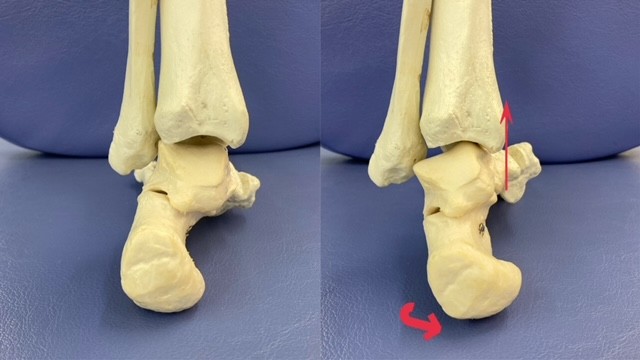

肉離れを起こしやすい

ふくらはぎの内側

(腓腹筋内側)を例にあげます。

右の骨盤が左より上がっている方

(骨盤の右挙上位)の場合

特徴として、

右の骨盤が上がっている分

地面までの距離が長くなります。

そのままだと地面に足が届かなくなるため

足の長さを、踵を外側に傾けることで

補おうとします。

(写真は左足です)

その状態が続くと内側の腓腹筋が短縮します。

ただし、ジャンプなどの着地動作は

基本的に踵は内側に傾きます。

この時、腓腹筋は逆に伸ばされます。

つまりスポーツ中の着地や

バックステップなどで、

通常より短縮している筋肉が

一気に力が入りながら伸ばされるため

肉離れのリスクが高まります。